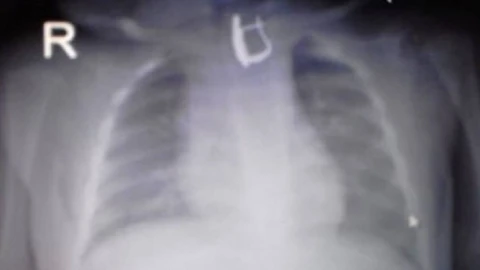

Рентген түсірілімінде баланың асқазанына әлдебір зат байқалды. Оның сырға екені белгілі болды.

Дәрігерлер эндоскопиялық жолмен баланың асқазанынан сырғаны алды. Қазір баланың жағдайы жақсы. Тыныс алып жатыр. Дер кезінде келген көмектің нәтижесінде баланы аман алып қалды. Баланың асқазаны жараланып, қанап үлгерген жоқ.